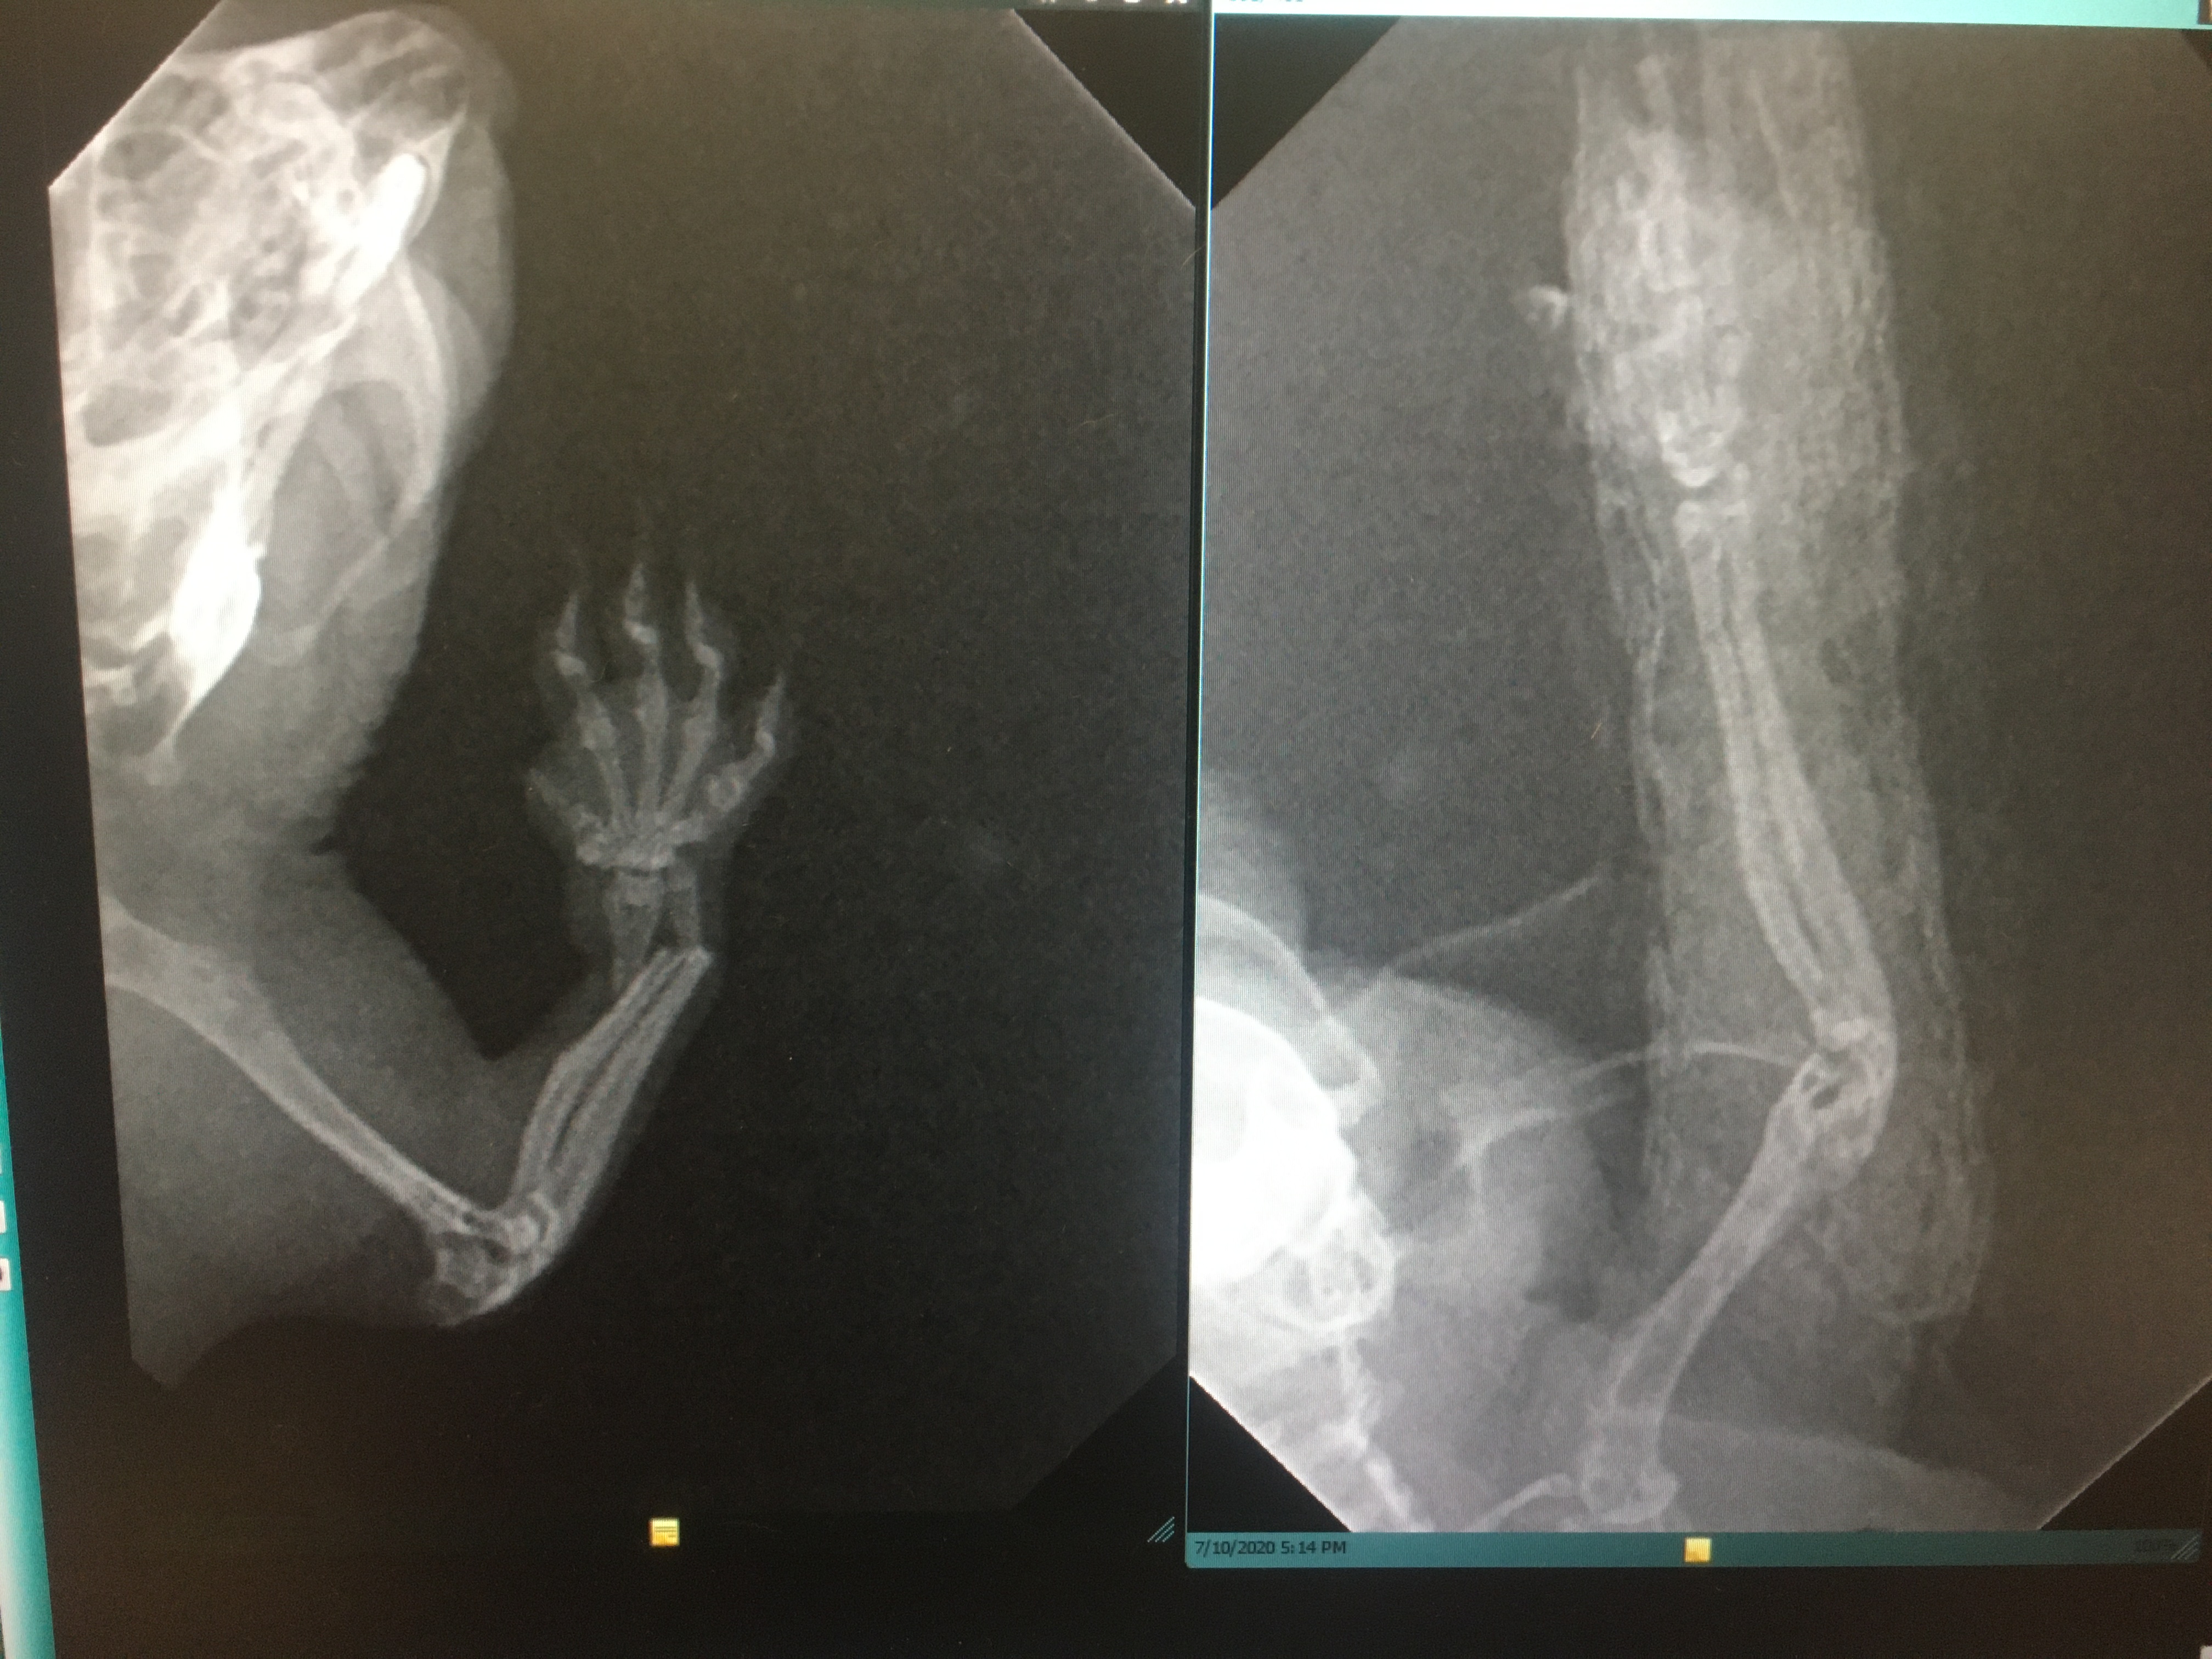

This is an actual case I’ve dealt with several times. For this little guy, I was able to place a tape splint under anesthesia for immobilization and then placed an Elizabethan collar made from old x-ray film and made sure he had excellent analgesia. He was back to burrowing and munching on pellets almost immediately. We used dental radiographs for initial diagnosis of the fracture and then post-splint placement to ensure good apposition of the fracture segments.

Because of their small size, we often don’t have the same options that are available in larger species like IM pins and external fixators, so we choose the option most likely to give us a good outcome. In similar cases, I’ve placed hypodermic needles as IM pins, or even amputated when the fracture was open and intensive management was going to be difficult for the owner.

In this case, he did great with the splint and we were able to remove it 3 weeks later to find a good callous had formed and he was using the limb normally.